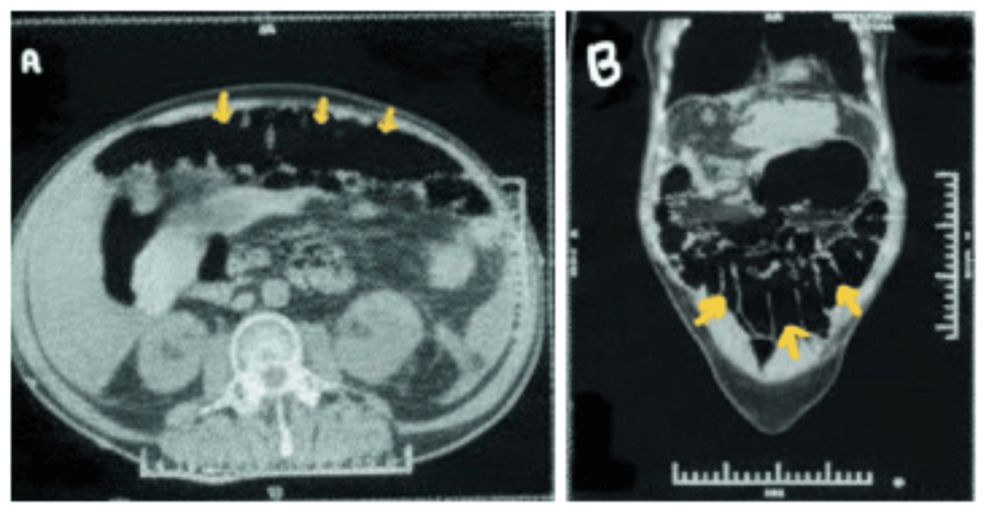

Approximately ten days into hospitalization, the patient developed abdominal distension, nausea, and inability to pass stool or gas. Initial imaging suggested a mechanical bowel obstruction.However, further examination revealed normal bowel caliber on CT scan, with marked colonic dilation – indicative of colonic pseudo-obstruction.

* Pathophysiology: Autonomic dysfunction associated with GBS can disrupt normal bowel motility, leading to pseudo-obstruction. The descending nature of the weakness and autonomic involvement likely contributed to this complication in our patient.

* Management: Conservative management with bowel decompression via nasogastric tube and rectal enemas was initially attempted. However, due to persistent symptoms and risk of colonic perforation, the patient required pharmacological intervention with prokinetic agents (e.g., metoclopramide) and, ultimately, temporary colostomy placement.